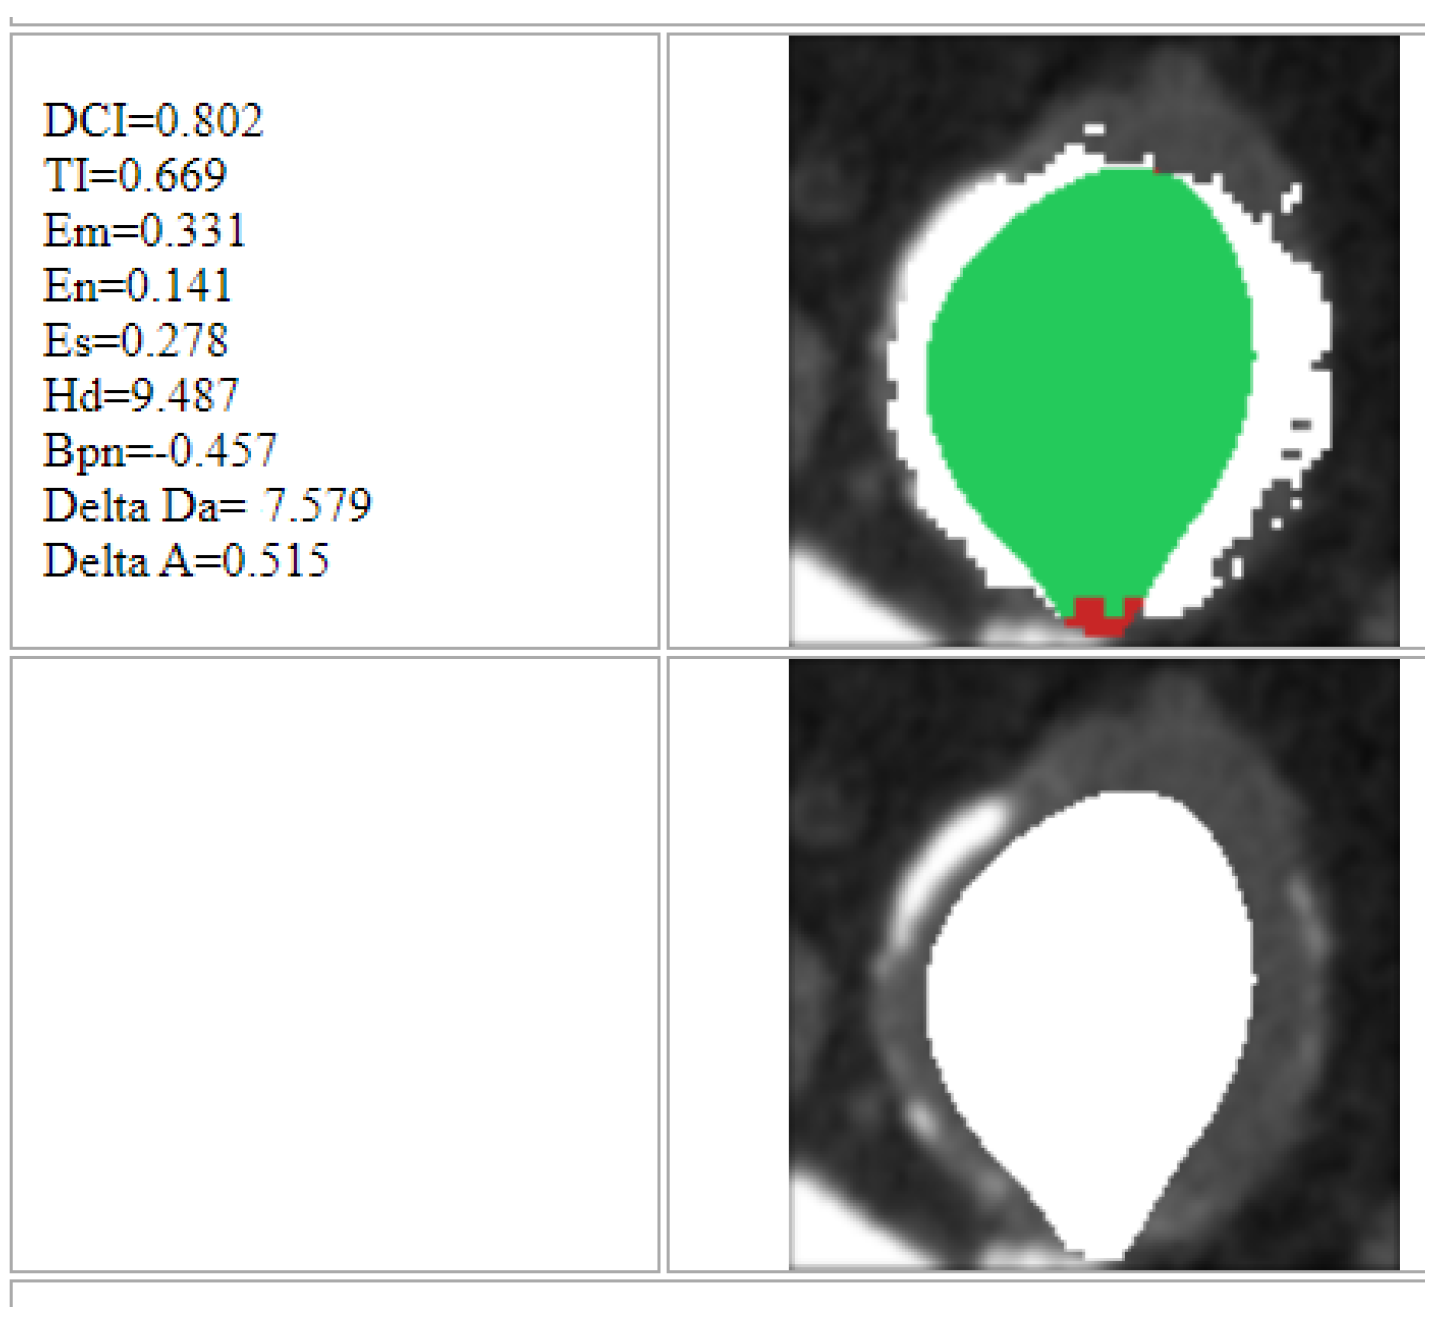

At the end of the process, the platform returns the results for each single image (slice), as shown in Figure 7. The zone marked by green indicates the area identified by the algorithm which is classified as correct, through comparison with the image with contrast medium. On the other hand, the red zone indicates the area wrongly identified by the algorithm and hence classified as incorrect. Furthermore, finally, the white zone indicates the area highlighted by the contrast medium but which the algorithm was unable to identify.

Figure 7. Results of the entire procedure.